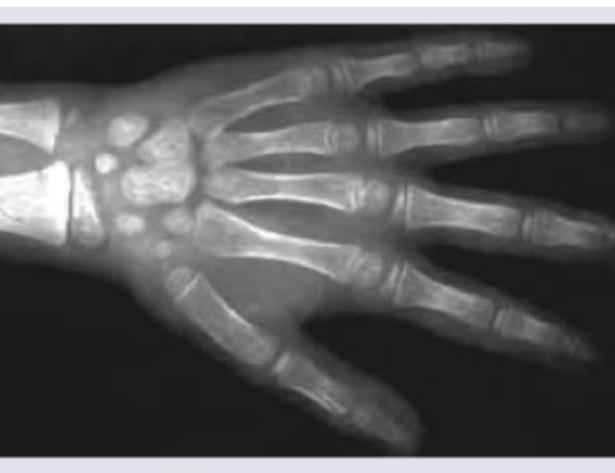

X-ray of wrist joint of an under-trial female convict who claims to be below 18 years was performed. The bone age of the patient as analyzed from the X-ray is: (Recent NEET Pattern 2016-17)

Explanation: ***Less than 18 years*** - The X-ray image shows that the **epiphyseal plates** at the distal ends of the radius and ulna, as well as in the phalanges and metacarpals, are still **open or partially fused**. - Complete fusion of these plates, especially the **distal radial epiphysis**, typically occurs around **18-19 years** in females, indicating the individual is likely under 18 years of age. *Less than 16.5 years* - The image shows a relatively mature skeletal structure where many of the **carpal bones** are fully ossified, and some epiphyseal fusion is evident, suggesting an age older than 16.5 years. - While still growing, the extent of development surpasses that typically seen at 16.5 years, where more distinct growth plates would be visible. *Less than 17 years* - Similar to the explanation for 16.5 years, the degree of **ossification** and **epiphyseal closure** observed, particularly in the carpals and partially in the long bones, implies an age beyond 17 years. - The image presents a more advanced skeletal maturity than commonly expected for someone definitively younger than 17 years. *Less than 21 years* - While complete skeletal maturity in some individuals can extend beyond 18 years, the significant **open growth plates** in the distal radius and ulna strongly indicate that the individual is not yet skeletally mature, which is generally achieved by 21 years. - If the individual were close to 21, these plates would be expected to be completely closed and fully fused.